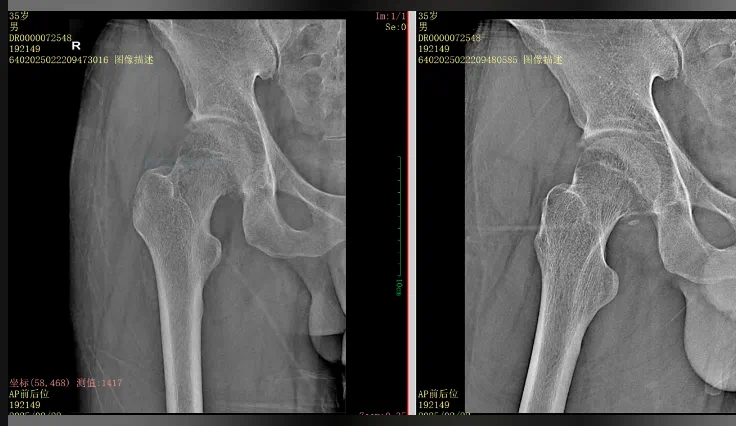

36岁的张先生(化名)因电动车追尾事故被紧急送往我院。右侧髋部剧烈疼痛、活动受限,右下肢短缩3CM,屈曲内收畸形。

影像学检查显示:右侧髋关节脱位、Pipkin IV型股骨头骨折及髋臼后壁骨折。

CT显示 股骨头骨折复位并不满意 ,需要手术 ,然而手术入路 、内固定方式又是问题。